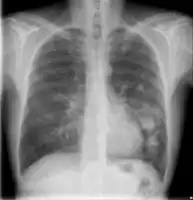

text: From left to right: Cryptococcosis lung, cryptococcosis brain | |

Cryptococcosis is a potentially fatal fungal infection of mainly the brain, where it appears as a meningitis, and the lungs, presenting as a pneumonia.[4][9] Cough, difficulty breathing, chest pain and fever are seen when the lungs are infected.[5] When the brain is infected, symptoms include headache, fever, neck pain, nausea and vomiting, light sensitivity and confusion or changes in behaviour.[5] It can also affect other parts of the body including skin, where it may appear as several fluid-filled nodules with dead tissue.[6]

Lung

Cryptococcus (both C. neoformans and C. gattii) plays a common role in pulmonary invasive mycosis seen in adults with HIV and other immunocompromised conditions.[15] It also affects healthy adults at a much lower frequency and severity as healthy hosts may have no or mild symptoms.[16] Immune-competent hosts may not seek or require treatment, but careful observation may be important.[17] Cryptococcal pneumonia has a potential to disseminate to the central nervous system (CNS) especially in immunocompromised individuals.[18]

Pulmonary cryptococcosis has a worldwide distribution and is commonly underdiagnosed due to limitations in diagnostic capabilities. Since pulmonary nodules are its most common radiological feature, it can clinically and radiologically mimic lung cancer, TB, and other pulmonary mycoses. The sensitivity of cultures and the Cryptococcal (CrAg) antigen with lateral flow device on serum are rarely positive in the absence of disseminated disease.[15] Moreover, pulmonary cryptococcosis worsen the prognosis of cryptococcal meningitis.[15]